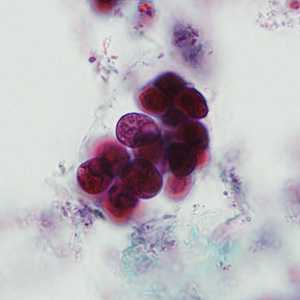

April - 2008 - Case #226

A 32-year-old Latin American man sought medical attention for persistent fever and cough. A sputum specimen was collected for testing. Smears were prepared and stained with Giemsa.